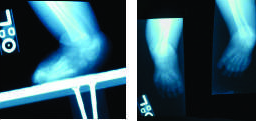

Первые два месяца ортез снимается лишь для гигиены ребенка, далее постепенно удаляется, сначала - на 2 часа, затем по нарастающей - до 8 часов и только в бодрствующем состоянии ребенка. При этом родители, заранее обученные, выполняют с ребенком пассивные упражнения для получения гиперкоррекции стопы. По достижении детьми 6-месячного возраста в обязательном порядке производится рентгенография стопы в прямой и боковой проекциях с упором (рис. 4).

При рентгенографии измеряются таранно-пяточный и пяточно-большеберцовый углы. Таранно-пяточный угол в норме составляет 30º как в прямой, так и в боковой проекциях, пяточно-большеберцовый – не менее 90º. При нормальных или близких к норме углах консервативное лечение продолжается ортезами того же типа до возраста, когда ребенок начинает стоять и ходить.